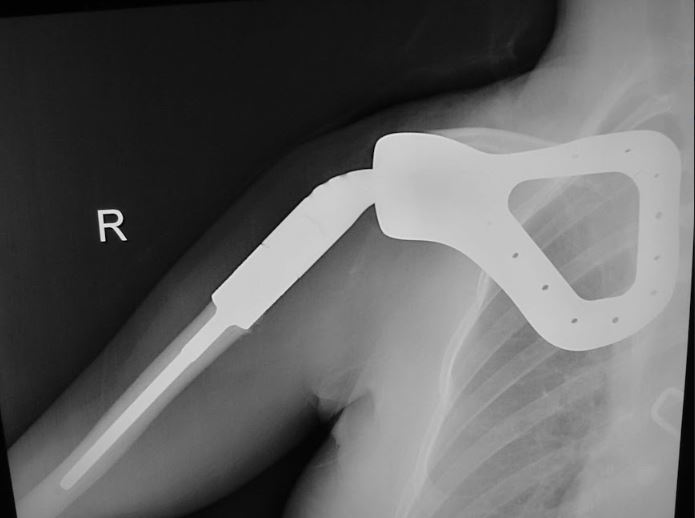

This image shows the total scapula prosthetic replacement as seen on an X-ray.

This is a second-generation scapular prosthesis. This allows the muscles a better area to attach in order to give the shoulder more stability.

The scapula prosthesis is placed with the upper part of the humerus prosthesis already seated in place. The humerus portion of the prothesis is cemented and then the scapula prosthesis is sutured to the chest wall. This allows for proper positioning and function of the arm.